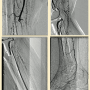

E. Scott: Last week I encountered an 80-year-old woman who was receiving inpatient treatment for a protracted pneumonia, further complicated by worsening rest pain and multiple ulcerations of her right toes. An arterial duplex demonstrated an occlusion of her right popliteal artery with evidence of additional tibial occlusive disease. Her ankle-brachial index was 0.38. I waited for her pneumonia to clear and then proceeded with formal angiography and intervention (Figure 1). Her initial angiographic images depicted a not-infrequent situation encountered in CLI patients — the absence of a healthy distal bypass target. Her dorsalis pedis artery was occluded, as was the common plantar artery. A short segment of the lateral plantar artery was identified in the foot that suggested this was likely the healthiest of the major pedal arteries.

I crossed the popliteal occlusion with a V-18 wire (Boston Scientific) and selected the posterior tibial artery with it. A 4mm Spider wire (Medtronic) was then positioned in the mid posterior tibial artery. I usually use some form of atherectomy in severely diseased popliteal arteries to minimize the risk of dissection and chose directional atherectomy (TurboHawk SX-C, Medtronic) for this lesion. Plain balloon angioplasty (2.5mm) was used for treatment of the distal posterior tibial lesions and the common plantar artery. A 2.0mm balloon was used for treatment of the lateral plantar artery. I completed the therapy with use of a 4mm drug-coated angioplasty balloon in the popliteal artery due to my perception of a high risk of restenosis in this segment.